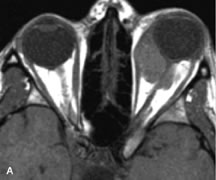

Extraocular muscle enlargement in patients with thyroid-associated orbitopathy is demonstrated equally well with CT and MRI studies. However, the superior tissue contrast on MR images reveals better details of the relationships of the optic nerve to the thickened muscles at the orbital apex (Fig. 16).50 In addition, MRI may be able to differentiate between muscles that are enlarged as a result of edema and active inflammation and those enlarged because of fibrosis by their T2 relaxation times.21 Quantitative MRI was not found to be accurate in predicting the success of low-dose orbital irradiation.51 However, a muscular index relating the diameters of the rectus muscles to the bony orbital dimensions was useful in predicting optic nerve compression.52

Fig. 16. A-C, T1-weighted MR scans obtained with a high-resolution surface coil demonstrate fusiform enlargement of the extraocular muscles. The medial, lateral, and inferior rectus muscles are especially involved. Note the relative sparing of the tendinous insertions, a finding characteristic of this disease process, as well as fatty infiltration of the lateral and inferior rectus muscles. There is marked proptosis, best visualized on the sagittal image (A), and mild crowding of the optic nerve at the orbital apex.